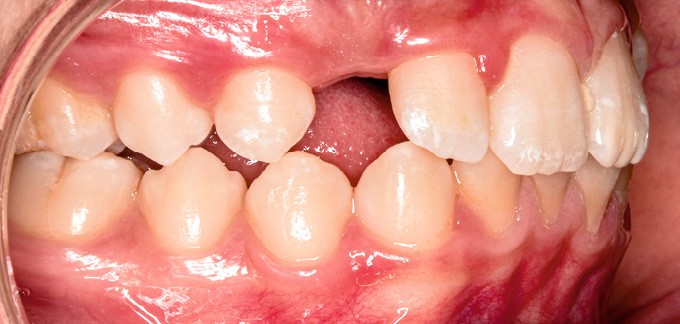

Sur le plan alvéolo-dentaire (fig. 1b) :

- Classe II subdivision gauche avec déviation du point inter-incisif mandibulaire à gauche ;

- occlusion inversée entre 22 et 32 ;

- dysharmonie dento-arcade (DDA) sévère ;

- 13 en position haute retenue.

Sur le plan squelettique : Classe II, schéma hypodivergent (fig. 1c). Sur le plan fonctionnel : aucune dysfonction ni parafonction.